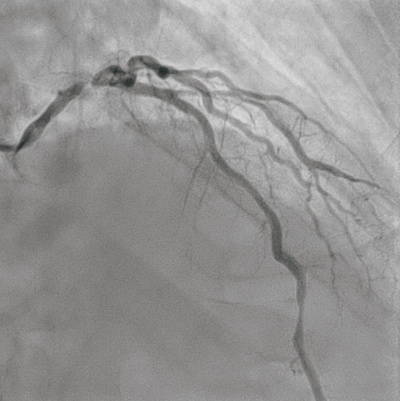

冠動脈造影像 を別に示す。血圧が低下したため、補助循環装置を挿入した。このときの胸部透視時の写真を別に示す。

c. 留置している補助循環装置により血液の酸素化が行える。

d. 留置している補助循環装置により冠動脈血流量の増加が期待される。

e. 留置している補助循環装置は大静脈内に留置されている。